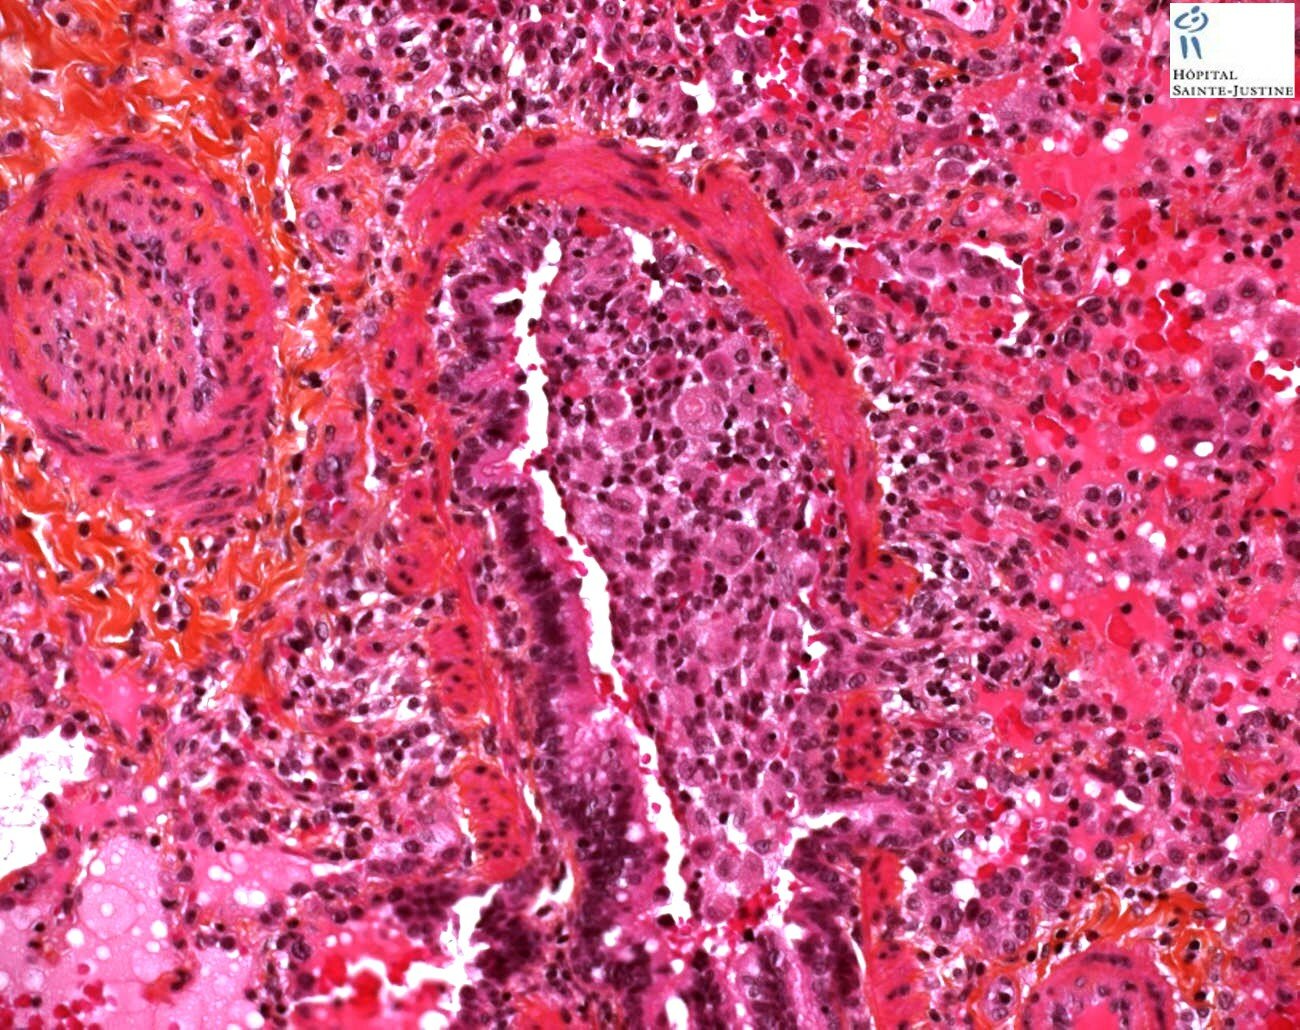

necrotizing bronchiolitis